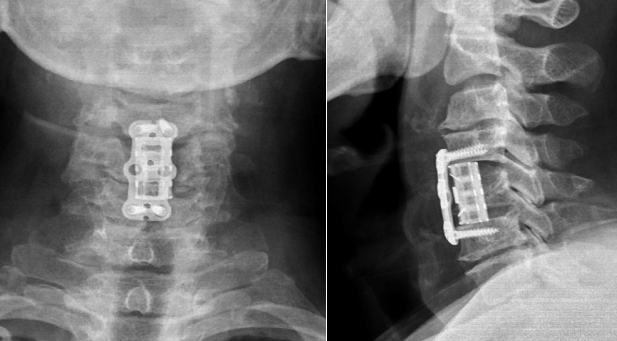

绵阳市骨科医院成功开展3D打印仿生颈椎人工椎体植入术

“真没想到手术效果这么好!折磨我十多年的病痛,你们2个小时就解决了。”近日,刚在绵阳市骨科医院接受3D打印仿生颈椎人工椎体植入术的患者高先生在复查时惊叹道。 今年69岁的患者高先生,十余年间饱受四肢麻木、行走不稳困扰,前期虽经多次保守治疗,但效果均不理想。近月来,因左上肢完全失能,恰逢回绵探亲...